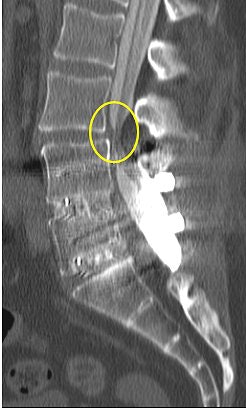

| Above, midsagittal T2-weighted MRI showed increase in stenosis at the L4 level by 2.0 mm with ventral thecal sac compression with axial loading (below). All images courtesy of Dr. Gerald Anzalone. |

| Increased conspicuity of L4-L5 disk bulge and 2.0 mm increase in stenosis at the L4-L5 level with axial loading. |